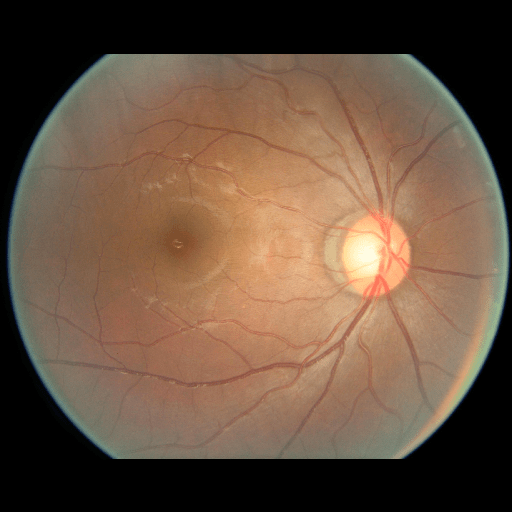

We conducted a case study on diagnosing diabetic retinopathy with ensembles of DL models. For benchmarking the performance of our ensemble-based solutions under the scheme described in Sec.3.3, we used two popular collections of diabetic retinopathy image data, the Kaggle Diabetic Retinopathy dataset [22] (hereafter referred to as “Kaggle-DR”) and the Messidor-2 dataset [23], each respectively consisting of and high resolution images. Diabetic retinopathy is graded into five SLs, as displayed in Figure 2. Following the problem setup used in previous papers [24], we trained models to distinguish the referable (SL2-4) cases from the non-referable ones (SL0 & SL1) (see Section B.1 for more detailed descriptions). We also tested our trained ensemble models on two o.o.d. image datasets (ImageNet [25] and CIFAR-10 [26]) to examine their capabilities of identifying o.o.d. inputs (see Section B in the supplementary materials).

The Kaggle-DR dataset comprises high resolution images. The presence of diabetic retinopathy is rated into five different SLs: no-DR (SL0), mild (SL1), moderate (SL2), severe (SL3), and proliferate (SL4), as illustrated in Figure 2. We divided the Kaggle-DR dataset into a development set and a test set, which respectively consisted of and images. The data in the development set were used to train and validate our Deep Learning (DL) models. The Messidor-2 dataset [38] that consisted of images was also used in our experiment as an additional dataset to test the true generalization performance of the models trained on the Kaggle-DR dataset. Images in Messidor-2 dataset were graded into the five SLs as in the Kaggle-DR dataset. Figure S.1 provides an illustration of the datasets used in our experiments.